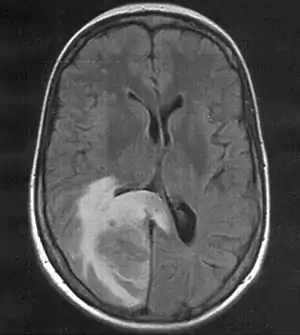

| Skull MRI (T2 flair) of a brain metastasis with accompanying edema | |